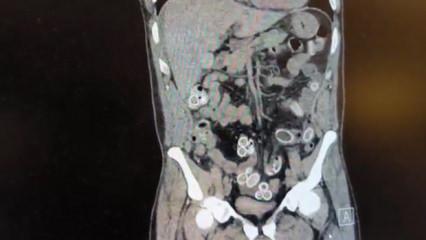

Fas’tan Beşiktaş'a midesinde uyuşturucu getirdi: Ameliyatla çıkarıldı